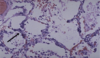

What does this show that is common in smokers and city dwellers? What substance accumulated? What can be negative effect in large amounts?

This shows carbon duse [anthracotic pigment] accumulation in lung

Can cause pulmonary fibrosis in large amounts